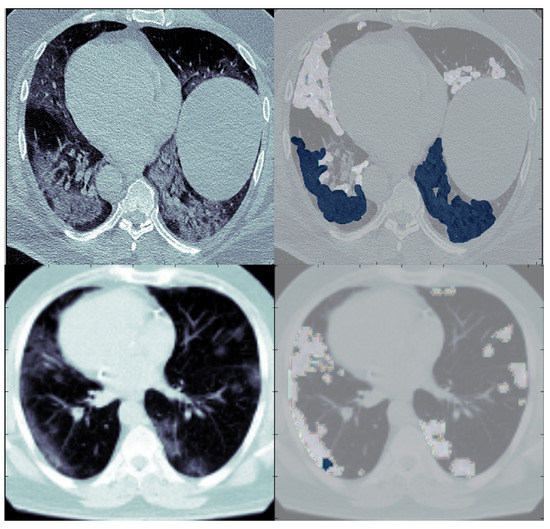

5.1. Preprocessing of MedSeg and Radiopaedia 9P Datasets

5.2. Preprocessing of Zenodo 20P Dataset